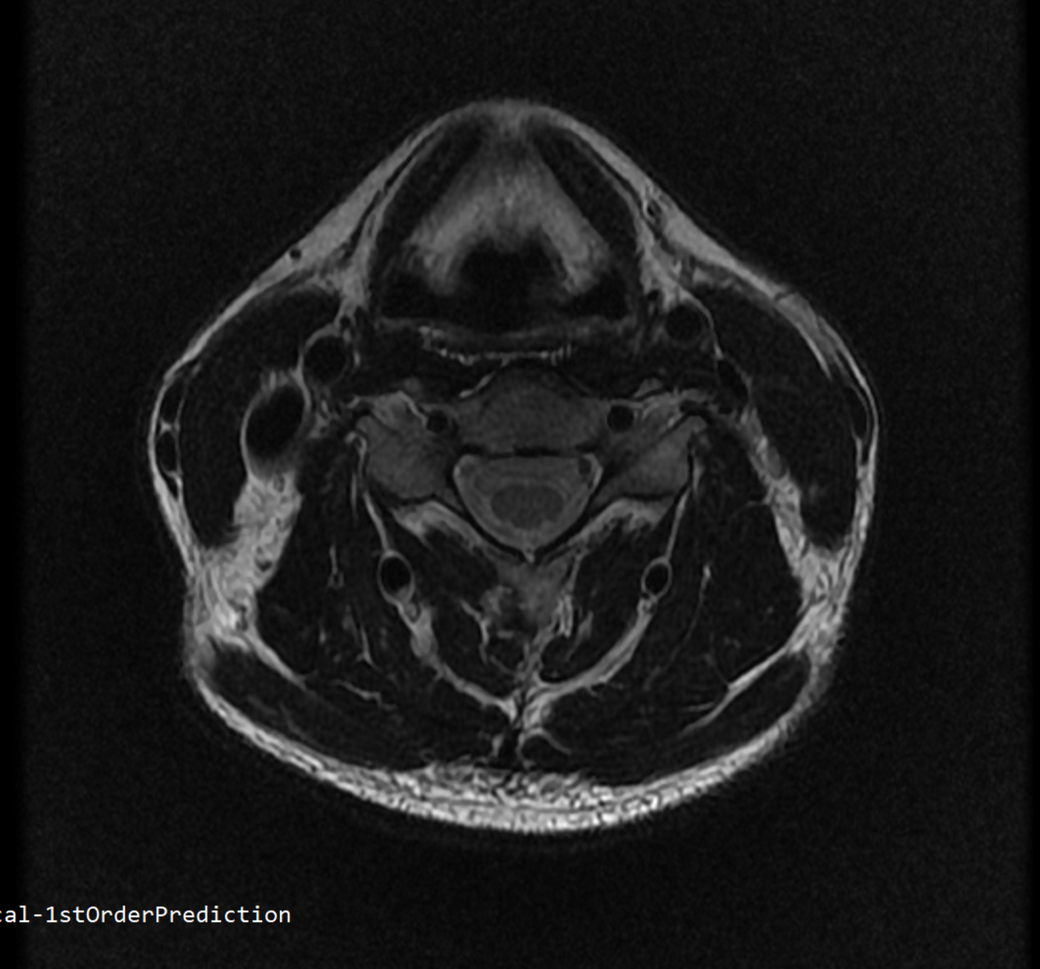

안녕하세요 목 경추 상단부터 순서대로 mri 촬영인데요

전체적으로 봐주시면 감사하겠습니다

• 1번 째 사진